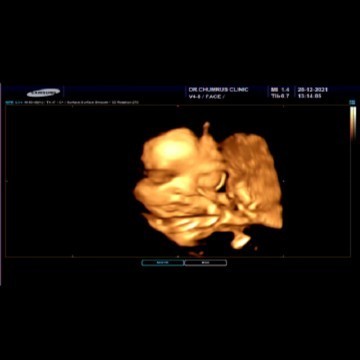

ได้ลูกสาว27วีคแล้ว แม่ๆช่วยตั้งชื่อหน่อยได้ไหมค่ะ ขอขึ้นต้น.ม.ม้า ความหมายดีๆ เป็นชื่อเล่นให้หน่อยค่ะ พี่ชายเค้าชื่อมิวสิค ถามน้องชื่ออะไร แม่นี่คิดไม่ออกเลย😂